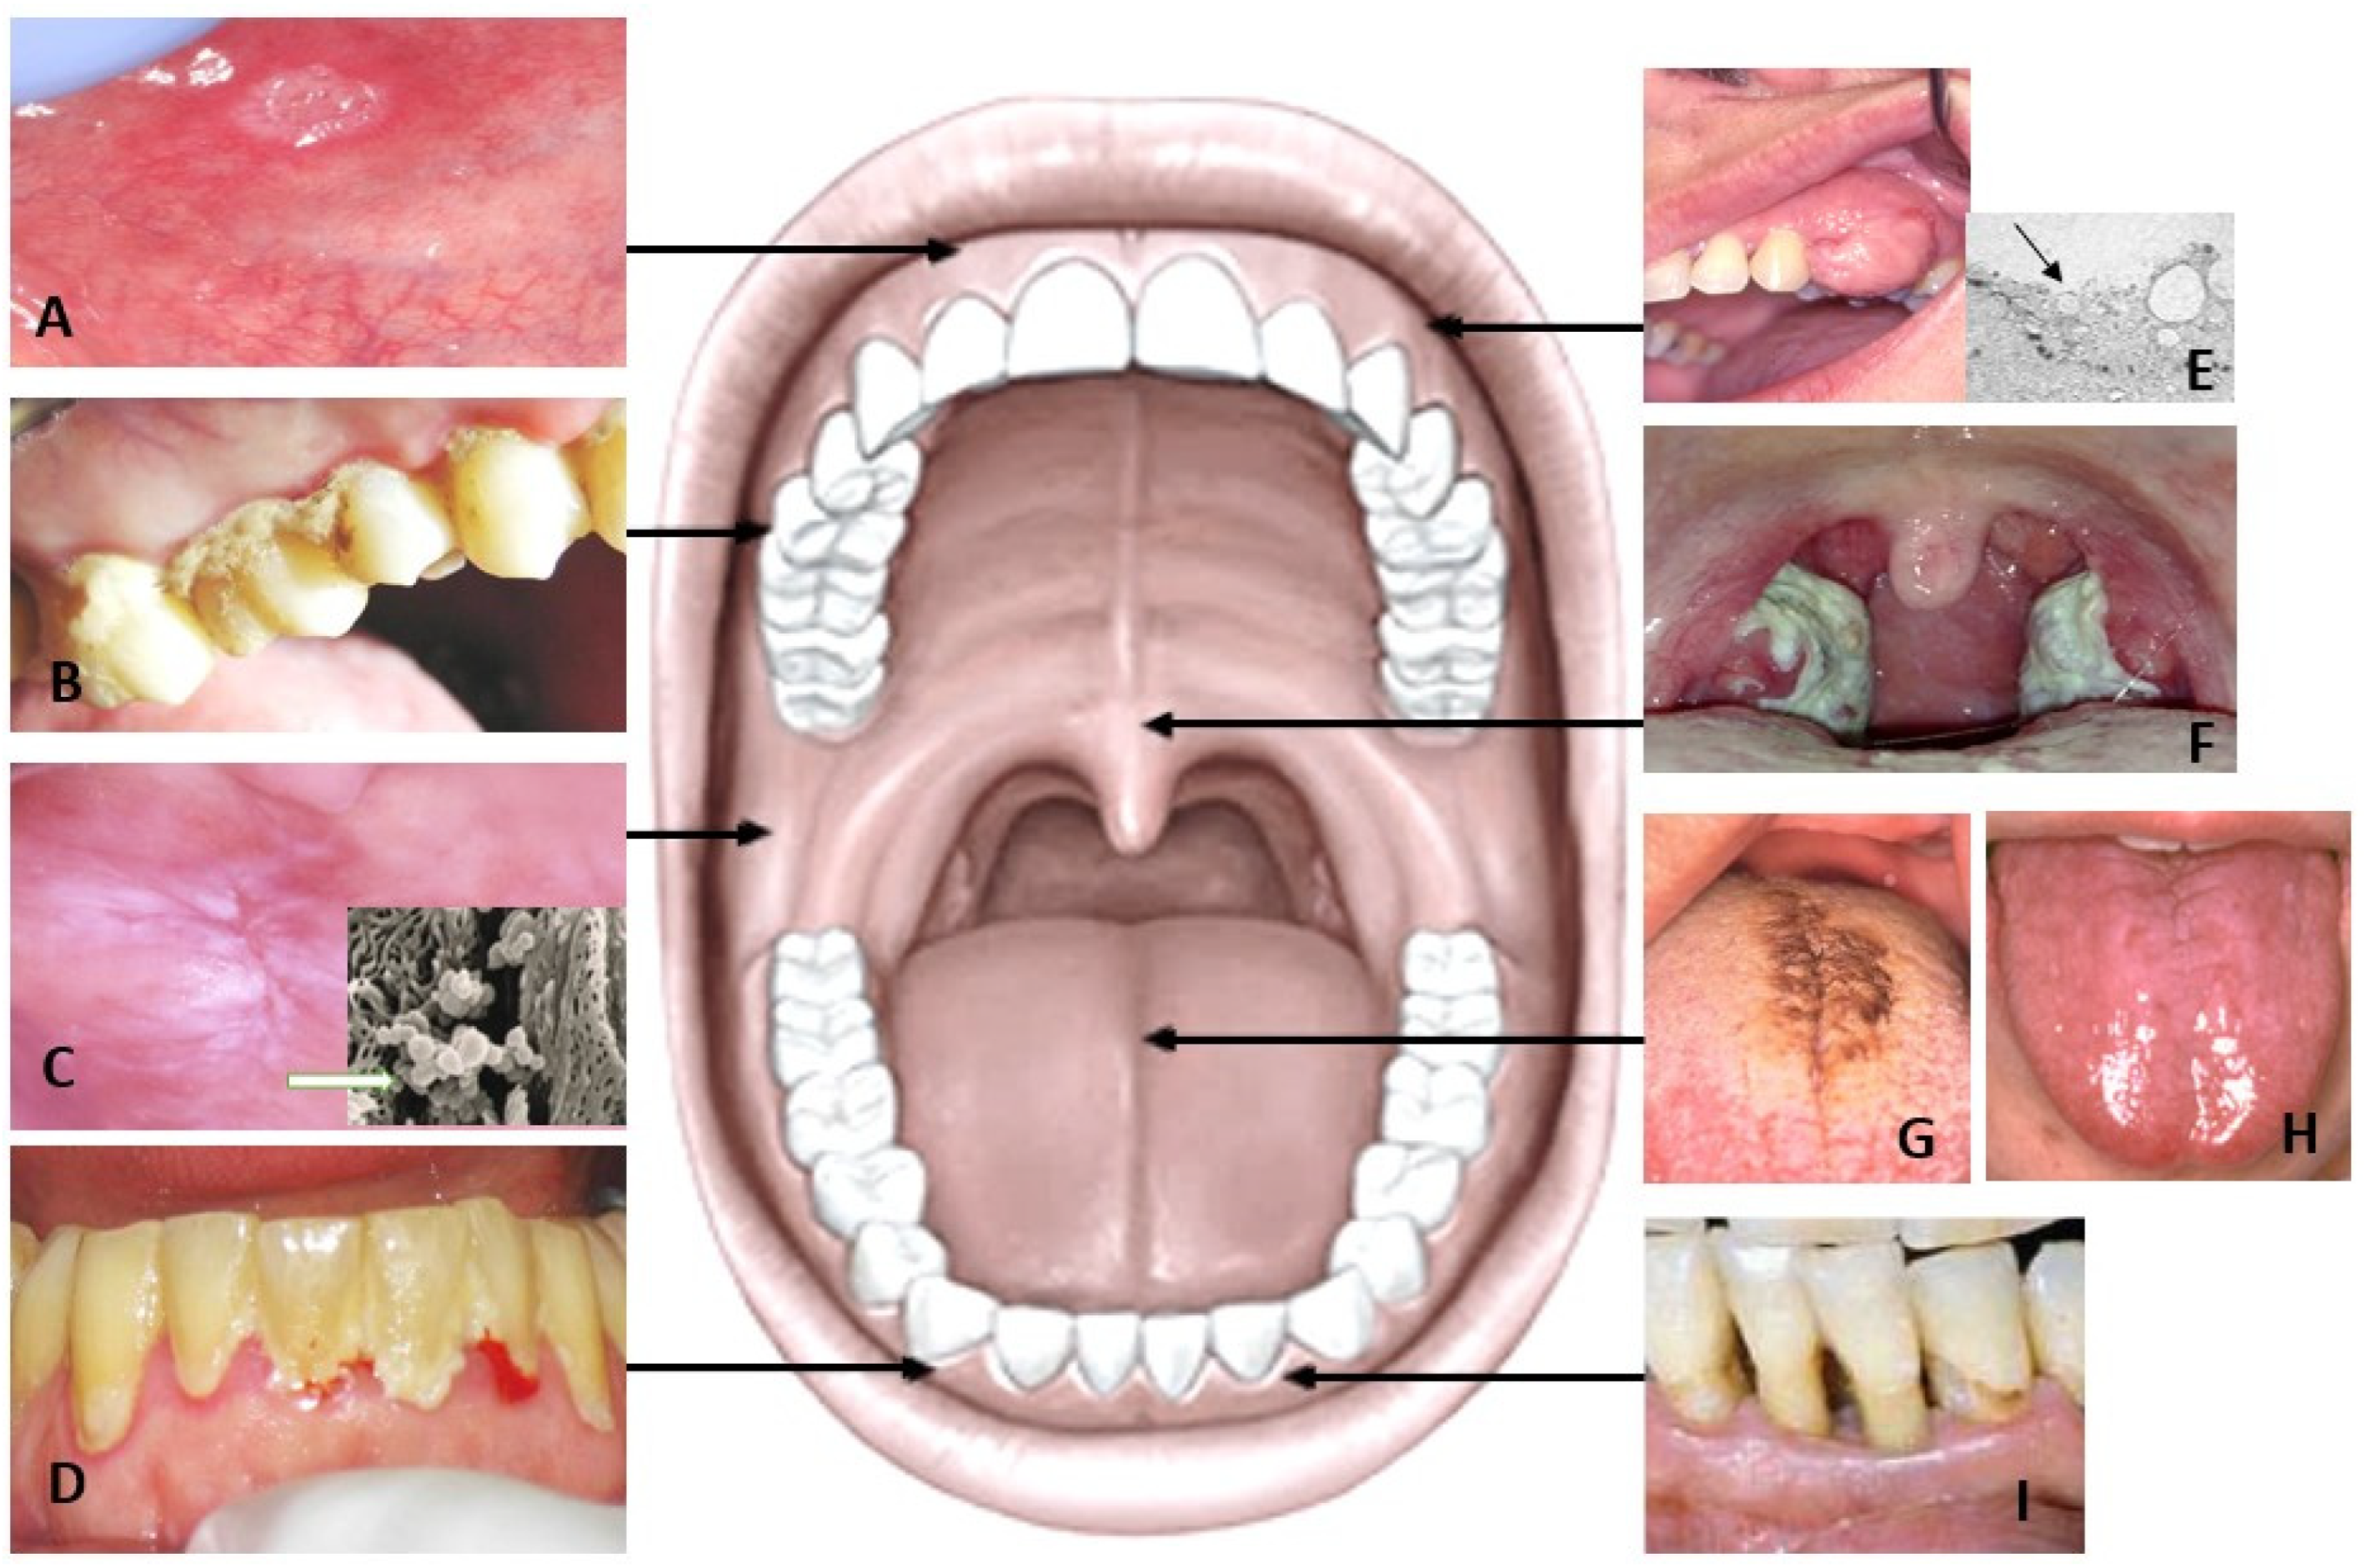

2. Sources of Salivary Metabolites in Healthy Subjects

3. Salivary Metabolites in Patients with Oral Inflammation

4. Salivary Metabolomics in Oral Mucosal Diseases and Oral Cancer

4.1. Tongue Disorders

4.2. Leukoplakia and Lichen Planus

4.3. Oral Cancer